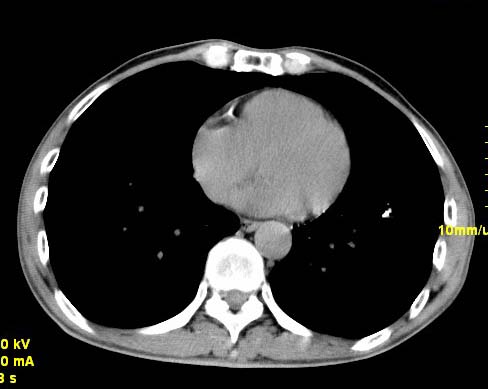

以下是引用wangzhengyuan在2007-11-11 23:31:00的发言:[br]钙化灶,看上去不像转移。

以下是引用zjzjr在2007-11-12 8:35:00的发言:[br]考虑错构瘤,建议定期复查.

以下是引用卜一在2007-11-12 5:59:00的发言:[br]病灶本身不像转移,不知有没有以前的胸部ct片,若有,则可以对比以下,若是新出现病灶,应高度警惕“转移”的可能![br]